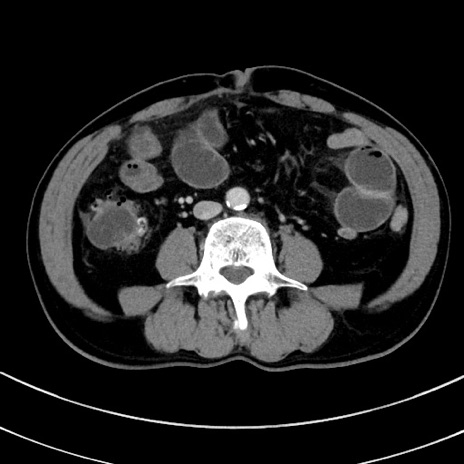

冠状断像

【症例】 60歳代男性

【主訴】 黒色吐物

【現病歴】 4日前から嘔気自覚、2日前の朝食後にも嘔気あり、自分で手で嘔吐反射起こし嘔吐したところ血が混ざっていたため受診。

【既往歴】 5年前汎発性腹膜炎を伴う急性虫垂炎で手術、高血圧、前立腺肥大症、高脂血症

【身体所見】 腹部正中に手術癩痕あり 腹部平坦・軟圧痛なし膨満感あり

【データ】WBC 8400、CRP 4.54